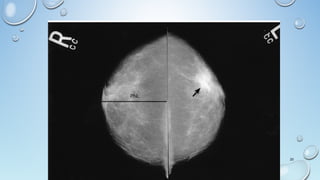

MASS

A 'Mass' is a space occupying 3D lesion seen in two different

projections.

If a potential mass is seen in only a single projection it should be called

a 'asymmetry' until its three-dimensionality is confirmed.

Shape: oval (may include 2 or 3 lobulations), round or irregular

Margins: circumscribed, obscured, microlobulated, indistinct,

spiculated

Density: high, equal, low or fat-containing.